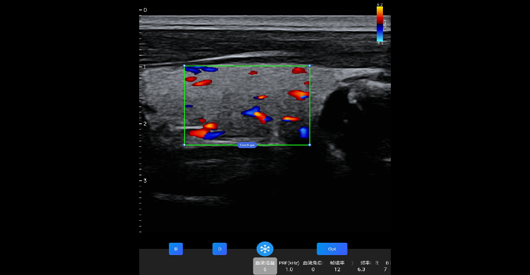

臂丛神经

探头类型:线阵探头。典型场景:血管、小器官。

甲状腺短轴

阵元基数:128。信号通道:64。

甲状腺长轴血流

中心频率:7.1 MHz。带宽范围:5-12MHz。